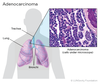

Qual o tipo de carcinoma broncogênico mais comum em não fumantes / mulheres / pacientes < 45 anos?

ADENOCARCINOMA

Qual o tipo de carcinoma broncogênico mais comum no geral?

ADENOCARCINOMA